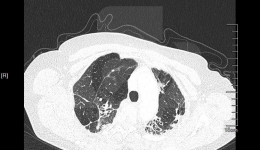

党的十九大报告指出:人民健康是民族昌盛和国家富强的重要标志。要完善国民健康政策,为人民群众提供全方位全周期健康服务。11月是全球肺癌关注月。11月22日早上8:30,我院胸外科党支部、呼吸科党支部、肿瘤科党支部、放射科党支部和药剂科党支...